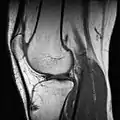

МРТ колінного суглоба.